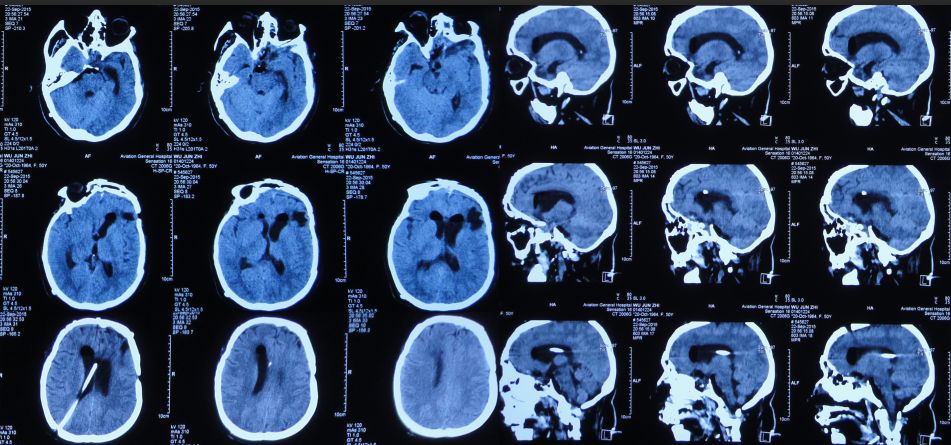

患者女,50岁,安徽省淮北市人。2014年12月14日,患者因高处坠落伤(2米左右)伤及头胸部及四肢,致昏迷,左耳、左鼻流血性液体,急诊前往安徽省淮南市潘集区某医院急查头CT显示左额叶脑挫伤、左侧颞骨凹陷性骨折、脑肿胀、颅内积气(图1);眼眶CT显示双侧眼眶内侧壁骨折(图2);胸部CT显示左侧肋骨骨折伴肺挫伤;右上肢X片显示右桡骨远端粉碎性骨折;左肩部X片显示左侧锁骨骨折。立即给予住院,保守治疗。

图1:2014年12月14日头CT:左额叶脑挫伤、左侧颞骨凹陷性骨折、脑肿胀、颅内积气

入院后第一天即2014年12月15日,患者神清,出现左眼肿胀,视力消失,左眼瞳孔增大,对光反射消失,左侧外耳道见澄清液体溢出,复查头CT:左额叶脑挫伤较前加重(图3)。

图3:2014年12月15日头CT:左额叶脑挫伤较前加重